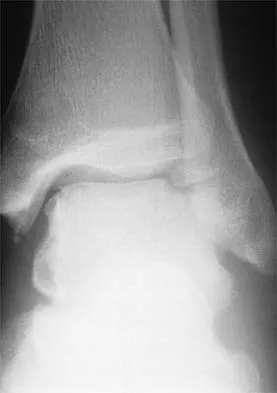

Figures 38a and 38b show the CT scans of a 64-year-old woman. What is the most likely diagnosis?

The CT scans show large cystic lesions in the talus and calcaneus with complete subluxation of the subtalar joint, allowing the calcaneus to slide laterally until it becomes blocked by the fibula. The cause of this subluxation is severe posterior tibial tendon dysfunction. Although no fibular fracture has yet appeared, it can occur with continued stress from the calcaneus. There is, however, a pathologic fracture in the medial calcaneus through a medial degenerative cyst. The joint space is irregular and not symmetrical as would be seen in an inflammatory arthropathy. Cystic lesions are not present in the tibia. No stress fracture is seen in the talus. Coughlin MJ: Sesamoids and accessory bones of the foot, in Coughlin MJ, Mann RA (eds): Surgery of the Foot and Ankle, ed 7. St Louis, MO, Mosby, 1999, pp 437-499.

- Anderson RB, Davis WH: Management of the adult flatfoot deformity, in Myerson M (ed): Foot and Ankle Disorders. Philadelphia, PA, WB Saunders, 2000, pp 1017-1039.